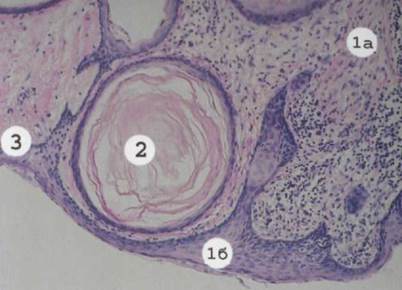

Гистологические изображения фолликулярной кисты яичника